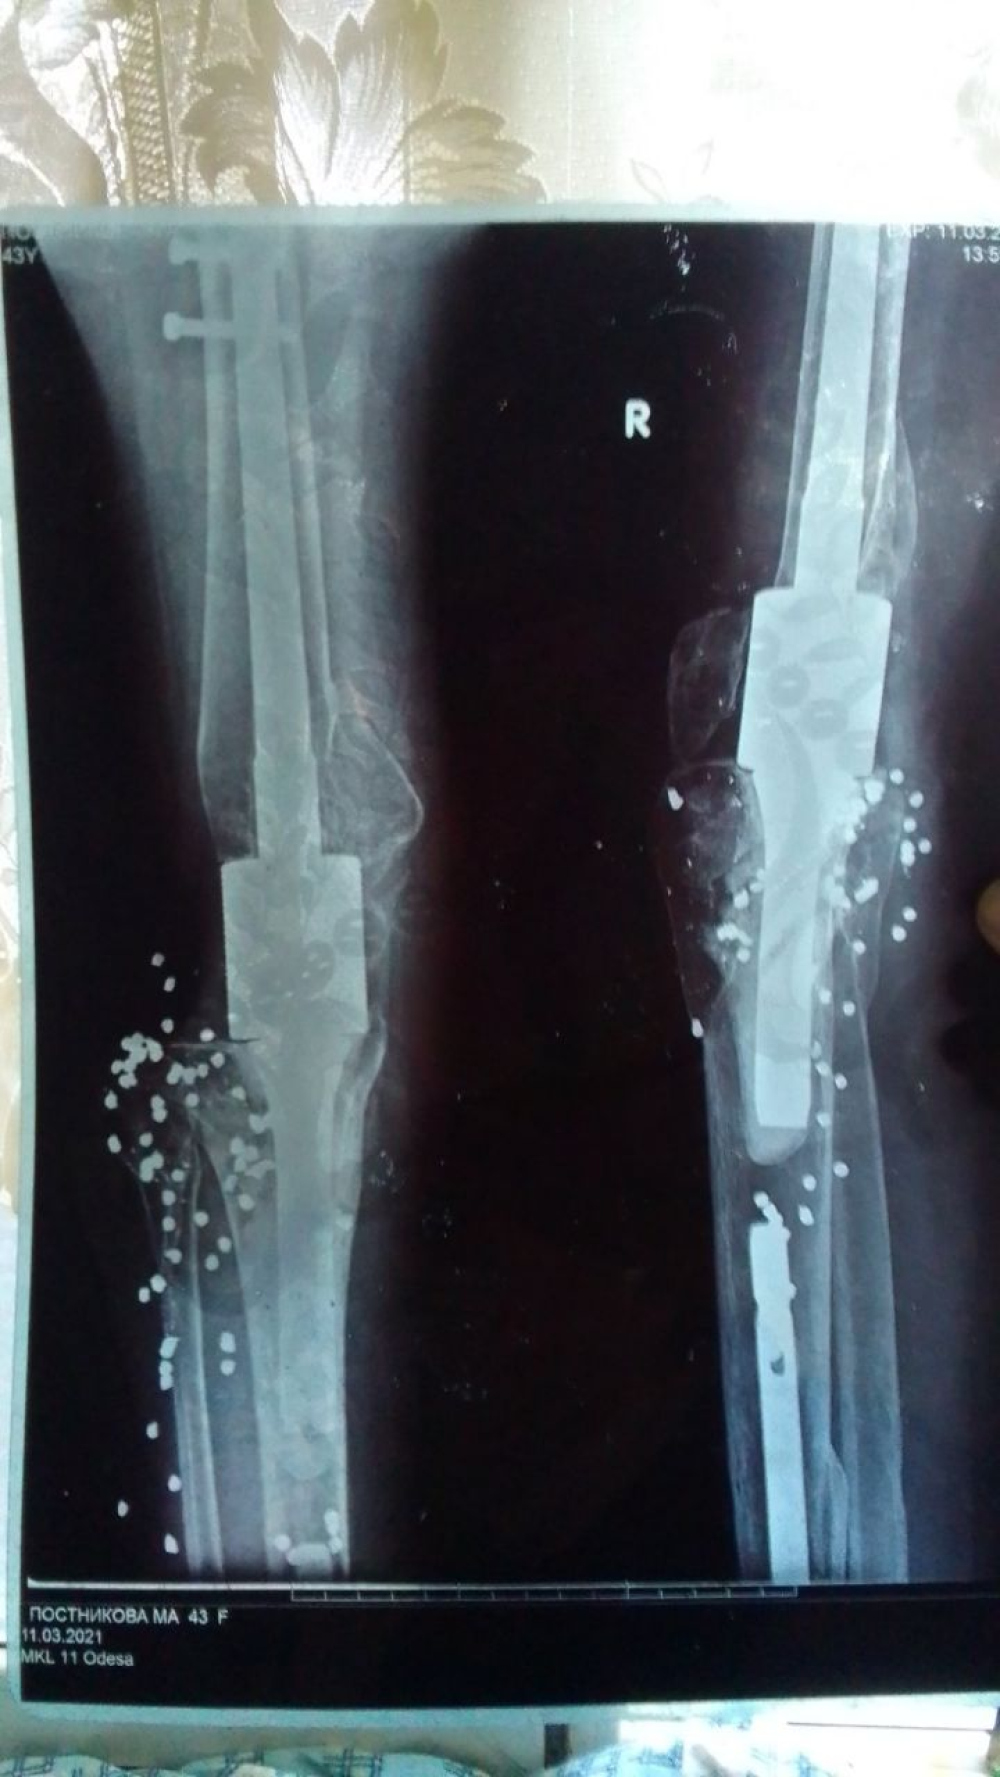

Спочатку лікарі сумнівалися, чи можна зберегти ногу: кістка була повністю роздроблена. Дрібні осколки довелося видалити під час операції, Марія залишилася без колінного суглоба і кількох десятків сантиметрів гомілки та стегнової кістки. У ній залишилося ще близько ста дробинок і шурупів, які не дістали на перших операціях. Медики подумували про ампутацію, але, на щастя, цього не сталося.

Протягом шести наступних років Марія Постнікова перенесла шість важких операцій. Але ногу відновити так і не вдалося — замість кістки їй поставили металевий штир, який не гнеться в коліні. На дорогий штучний колінний суглоб грошей в одеситки, яка залишилася одна з неповнолітньою донькою і літньою мамою, не знайшлося. Ані Олег Недялков, який поранив її з обрізу, ані Олександр Гребенча, який затулився нею, ні копійки на лікування не дали.